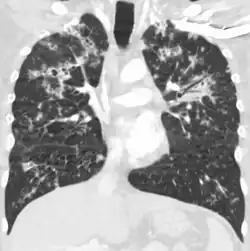

A case of miliary tuberculosis in an 82-year-old woman:

-

X-ray, 13 days after onset, showing bilateral interstitial infiltrates -